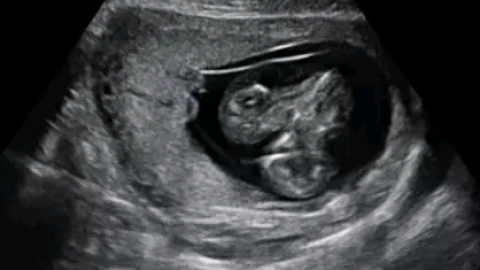

多胎妊娠

一次妊娠同时有两个或两个以上胎儿时称多胎妊娠。高危妊娠。本节主要学习双胎妊娠。胎囊中隔由两层血型相同或不同。一步检查胎儿性别、血型。(4)胎位多为纵产式3、辅助检查⑴B超检查:最早于孕6周在宫内发现两个妊娠囊,孕9周时见两个原始心管搏动。以合并羊水过